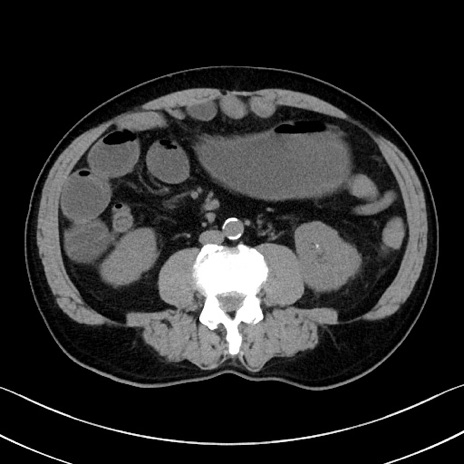

症例35(横断像)

【症例】70歳代 男性

【主訴】腹部膨満、嘔吐

【現病歴】昨日より腹部膨満感出現。本日増悪し、仙痛出現。嘔吐あり、受診。

【既往歴】糖尿病、胆摘後

【身体所見】BP 149/80mmHg、HR 74/min、BT 35.9℃、腹部:膨満、軟、圧痛なし。腸雑音減弱あり。上腹部正中切開瘢痕あり。

【データ】WBC 13500、CRP 1.72